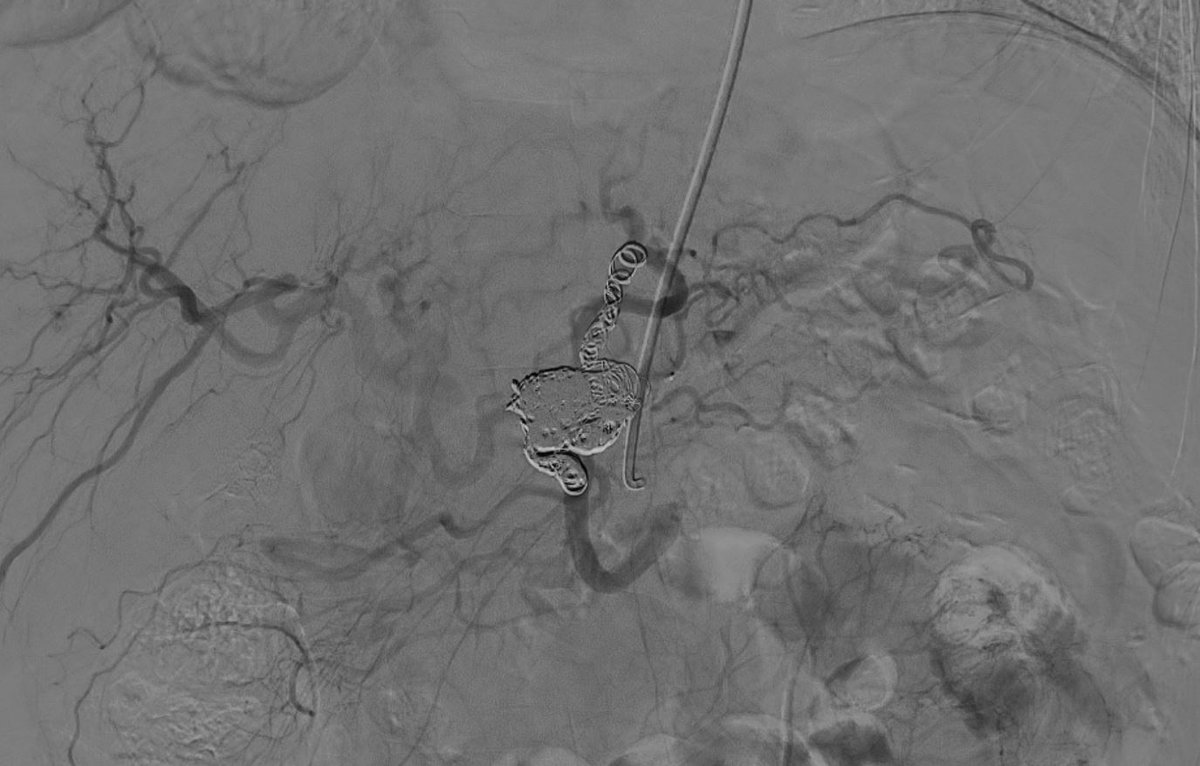

Pancreatic

#AVM with multiple arterial feeders and single outflow into splenic vein branch. Treated via#transportal approach with#coils and a plug. No more AVM. Fun way to start 2020.@MountSinaiIR@GESTSymposium@SIRspecialists@SIRRFS@ISETNewspic.twitter.com/1KRDZIJlPSHvala. Twitter će to iskoristiti za poboljšanje vaše vremenske crte. PoništiPoništi -